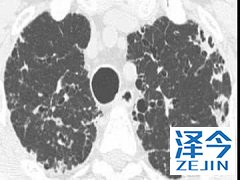

患者使用尼达尼布会产生较强的副作用吗 尼达尼布治疗特发性肺纤维化的作用已经得到了FDA的认可,并且已经批准上市。通过降低患者的用力肺活量来改善患者的肺功能,并且维持在一个比较稳定的状态,与使用安慰剂的患者相比,尼达尼布对于患者肺部的作用大概是安慰剂组患者的两倍。

尼达尼布的研制公司勃林格殷格翰一直在为遭受破坏性疾病的患者努力提供治疗的方案,并且还研究了尼达尼布治疗伴有间质性肺疾病的系统性硬化(SSc-ILD)以及进行性纤维化间质性肺疾病(PF-ILD)的疗效,相信在不久的未来会有更多的药物研发并且上市。

尼达尼布的作用已经得到了认可,并且广泛用于临床的治疗当中,由于我国还没有上市这一药物,患者还是需要到国外进行购买,虽然在使用的过程中可能会出现副作用,不过加以适当的控制还是能够被接受的。